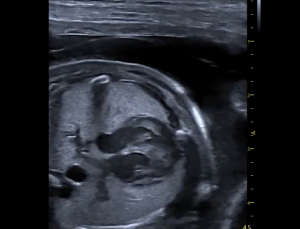

Breeder Ultrasound